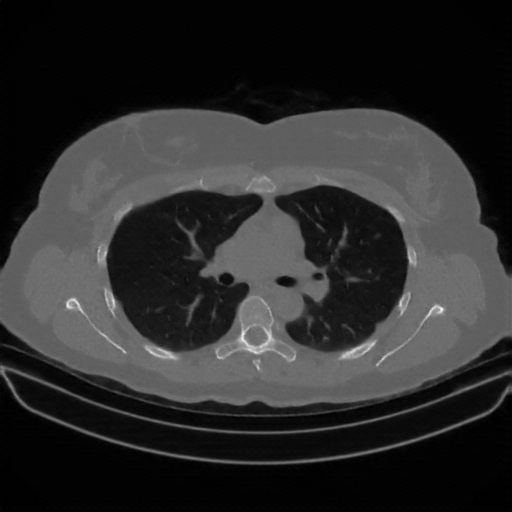

Generated VENOUS CT scan (A→B translation)

Full window (WL 1023.5, WW 4095 β†’ Low βˆ’1024, High +3071)

Actual HU range: [-1024.0, 1442.8]

Lung window (WL -600, WW 1500 β†’ Low βˆ’1350, High +150)

Actual HU range: [-1193.4, 150.0]

Mediastinum window (WL 40, WW 400 β†’ Low βˆ’160, High +240)

Actual HU range: [-160.0, 240.0]